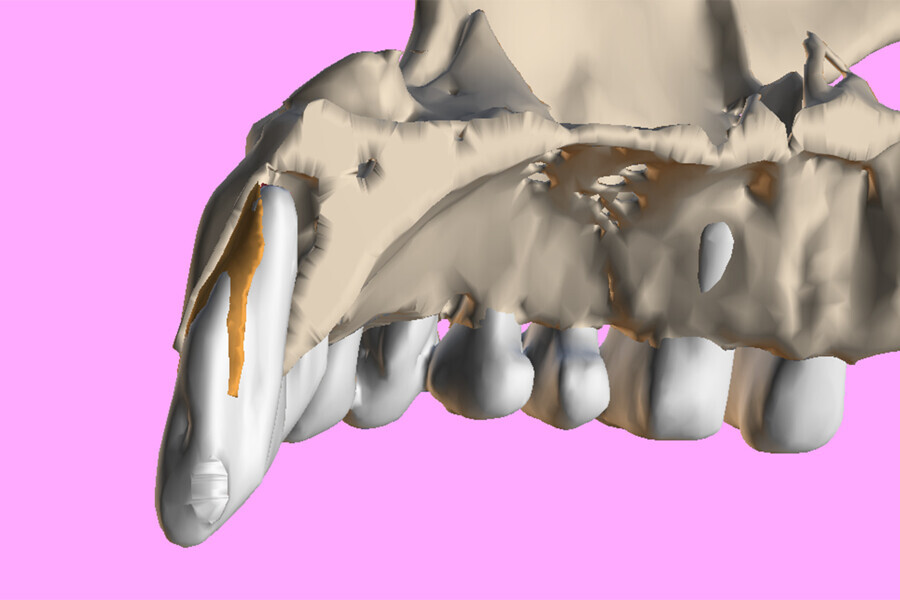

Fig. 4: The segmented root (white) and the root fragment (brown) within the sectioned maxillary surface model.

Fig. 5a: Virtual sectioning of the segmented root using Meshmixer with a simulated custom implant to reach the root apex.

Fig. 5b: The apical portion of the simulated AnyRidge implant can then be positioned so as not to touch the root fragment while engaging in host bone for stability.